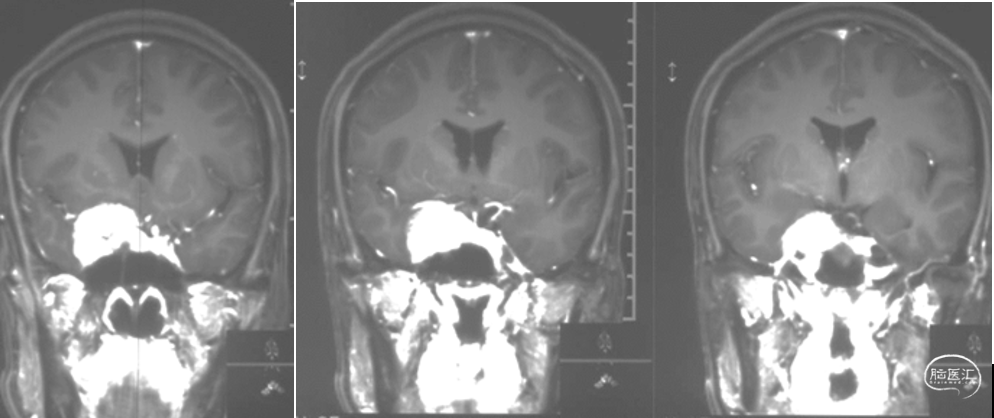

术前影像学检查

头颅MRI+增强